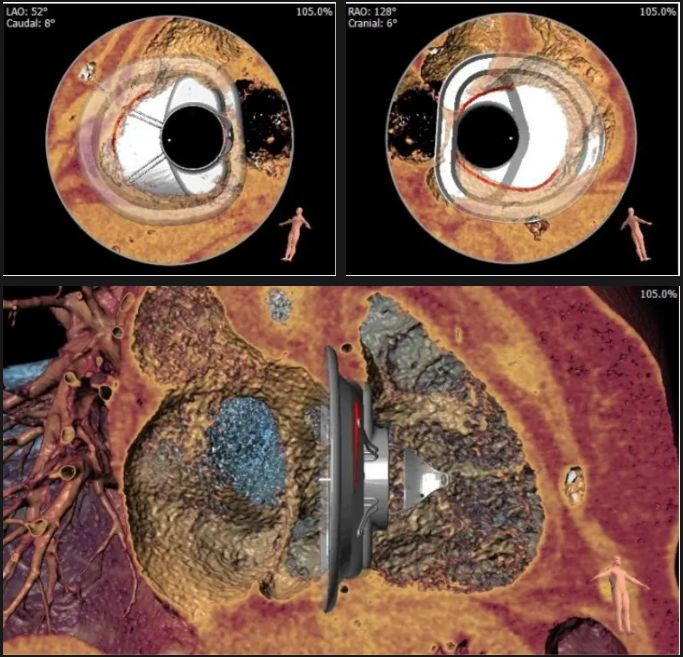

術前心臟CT評估

三尖瓣環平均周長徑54.3mm,最大直徑57mm

心房側周長平均徑(封堵高度)74.0mm

三尖瓣環切線位夾角 103°

術中經食道超聲輔助下可見LuX-Valve Plus夾持件抓捕瓣葉狀態良好,夾持件在位,室間隔錨定位置良好,假體瓣膜整體錨定狀態穩固。

術后三維超聲

術后即刻經食道超聲可見,三尖瓣假體瓣膜位置合適,牛心包瓣葉運動狀態良好,開閉正常,瓣周及瓣葉對合緣處未見明顯返流,心電圖及心包狀態較術前無明顯變化。